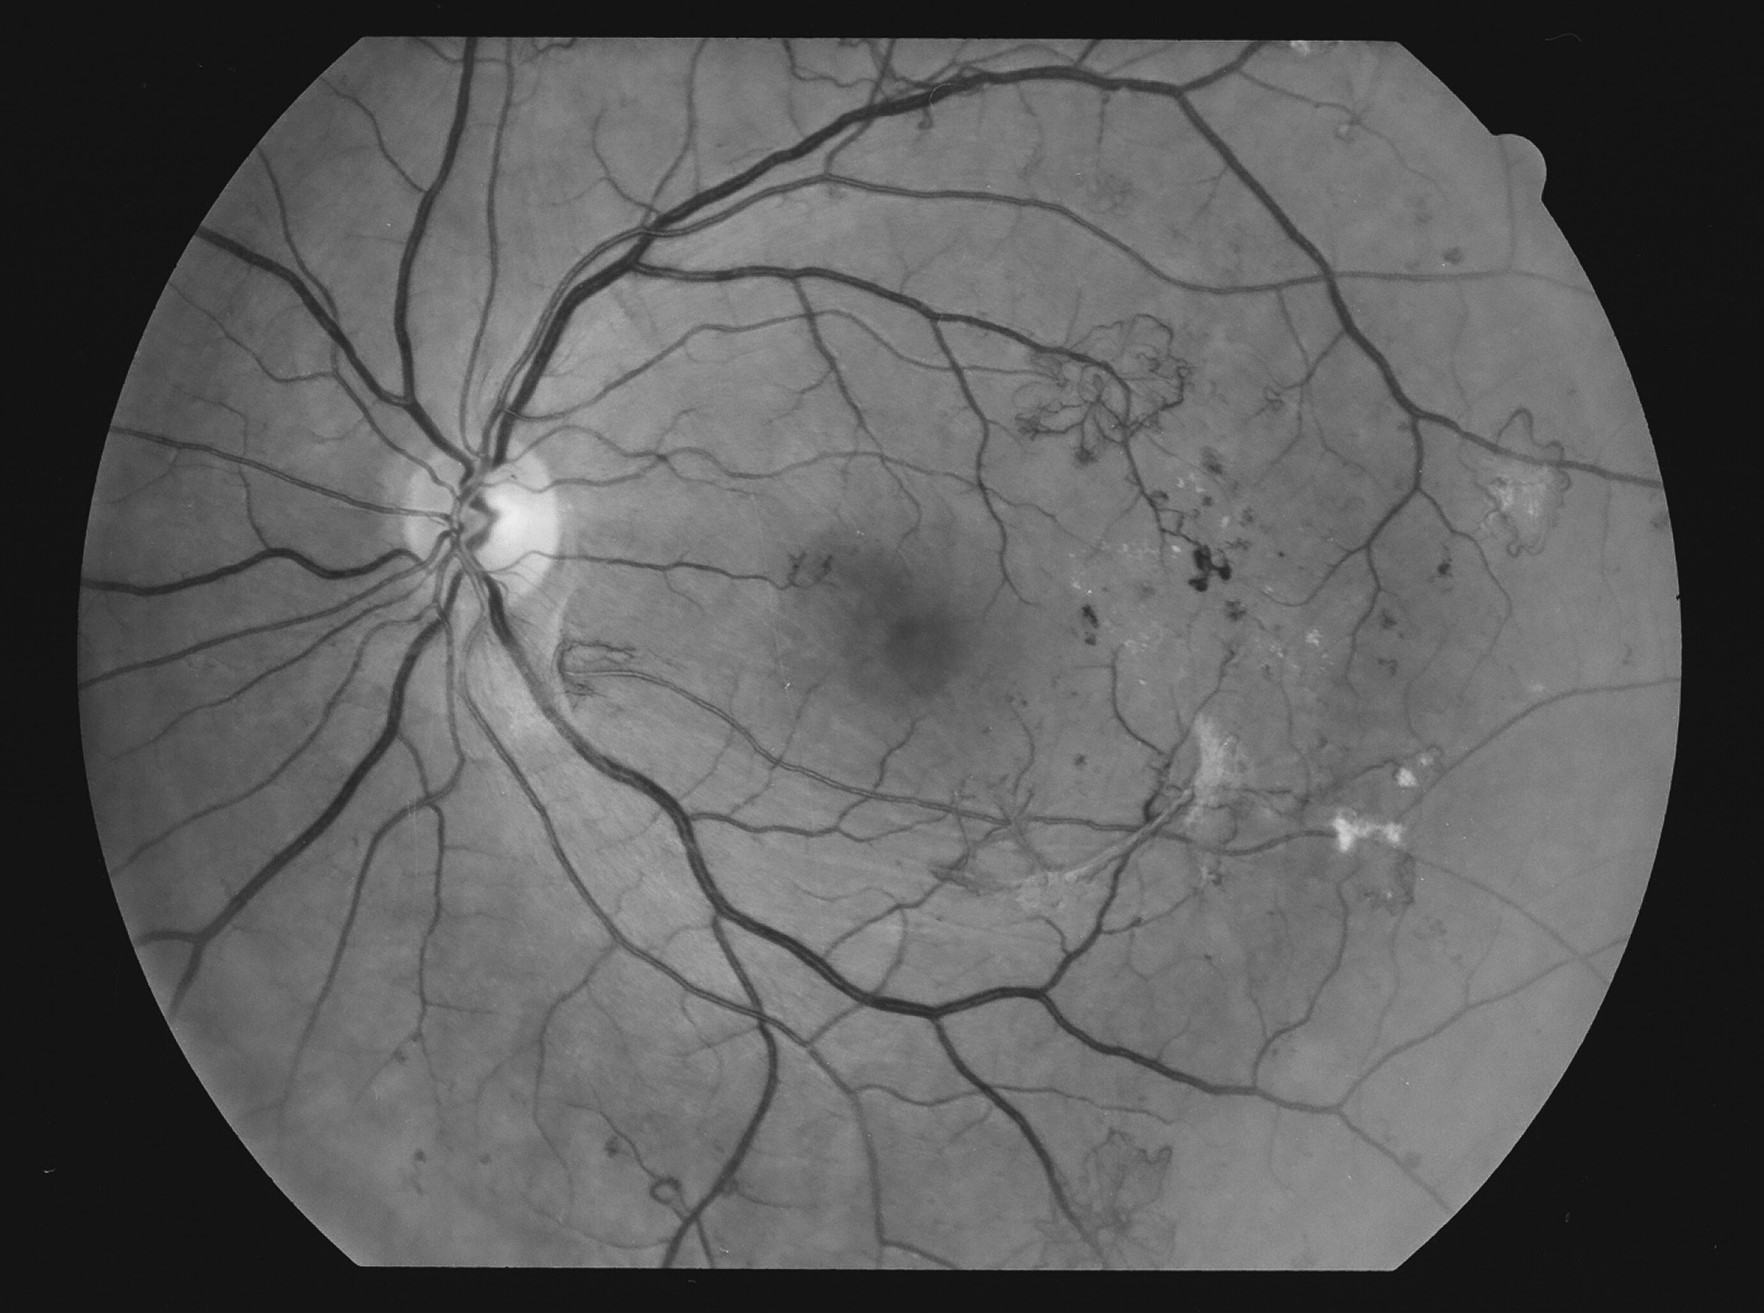

Kuva 8.

Diabetes, proliferatiivinen retinopatia, oikea silmä. Mikroaneurysmia, mikroinfarkti, IRMA:a ja uudissuonikasvua temporaalisesti.